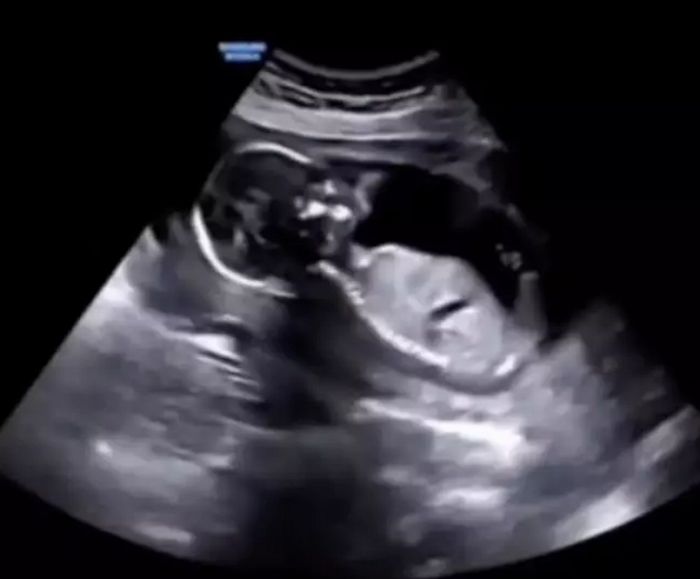

[인사이트] 김나영 기자 = 태어나 처음 보는 진귀한 영상이 SNS 상에서 뜨거운 반응을 불러일으키고 있다.만삭의 엄마가 신나서 웃을 때 배 속 아기의 모습을 촬영한 초음파 영상이 바로 그 화제의 주인공이다.지난 19일(현지 시간) 온라인 미디어 타일라(Tyla)는 엄...

엄마가 신나서 웃을 때 배 속 아기는 이런 모습이다 (+ 초음파 영상)